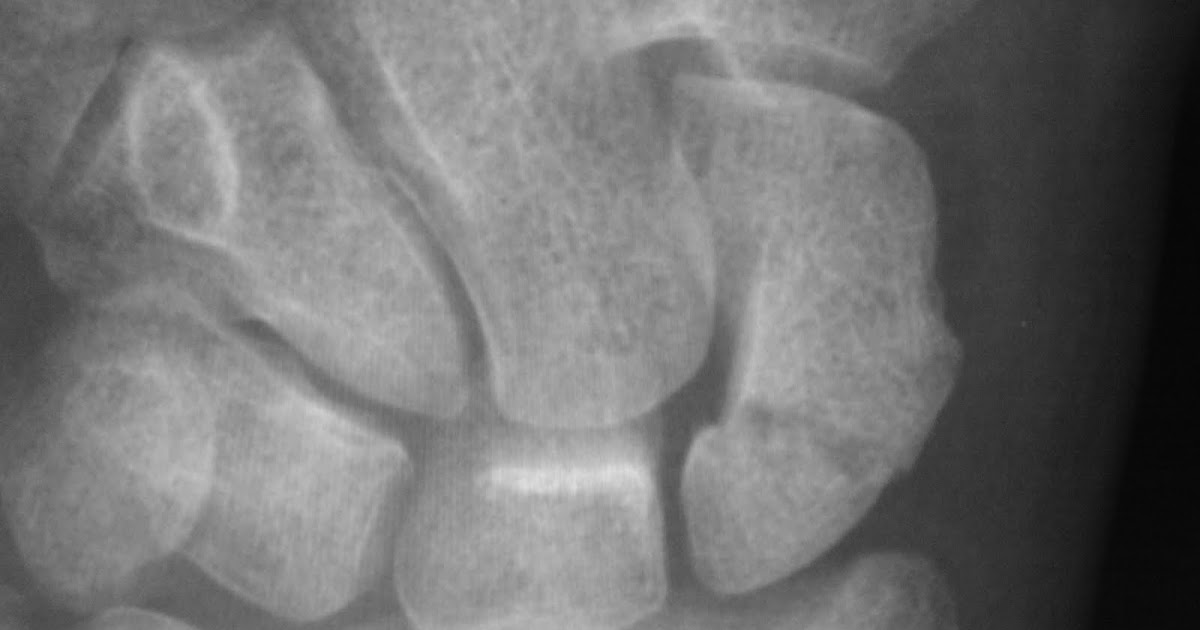

Daily Dose Avascular necrosis of scaphoid

What Is Avascular Necrosis Of Scaphoid Avascular necrosis (avn) is the death of bone tissue due to a lack of blood. Avascular necrosis (avn) of the scaphoid predominantly occurs in the proximal. Avascular necrosis is the death of bone tissue due to a lack of blood supply. Imaging tests can help pinpoint the source of pain. Avascular necrosis (avn) is the death of bone tissue due to a lack of blood. There may be poor retrograde blood flow from the distal to the proximal scaphoid. This technique is an attractive, minimally invasive alternative for nonunion and avascular necrosis resulting from fractures of the proximal pole of. Scaphoid is the bone of the wrist most frequently fractured. Also called osteonecrosis, it can lead to tiny breaks. Many conditions can cause joint pain. Some 10% of scaphoid fractures have associated fractures of other. In fact, there is a risk that fractures of the proximal scaphoid will completely disrupt the blood supply, causing part of the scaphoid to necrose, or die.